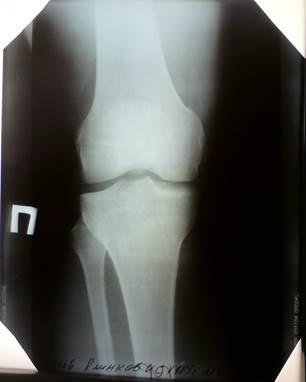

Рентгенограмма правого коленного сустава в двух проекциях

от 22.09.2010г.:

Форма сустава не изменена. Контуры четкие. В боковой проекции наблюдается затемнение костных структур, в связи с отеком. Межмышечные пространства расширены, в связи с отеком мягких тканей.

Боковая проекция

Прямая проекция

4) результатов дополнительных методов исследования: Рентгенограмма правого коленного сустава в двух проекциях от 22.09.2010г.: форма сустава не изменена. Контуры четкие. В боковой проекции наблюдается затемнение костных структур, в связи с отеком. Межмышечные пространства расширены, в связи с отеком мягких тканей.